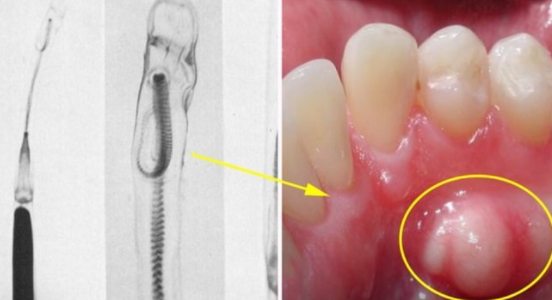

また、除去して調べたところ、それはイカの精莢(せいきょう)という、内部に精子の詰まったカプセルだったといいます。

そのうちの一つ、「日本口腔外科学会雑誌」に掲載された論文「生イカの精莢による口腔粘膜刺創の1例」を見てみると、白い精莢が舌や頬の肉に刺さった痛々しい写真や摘出された精莢の写真が掲載されています。

精莢は5~20mmほどの長さで、先端は矢じりのようになっていて簡単には抜けない構造になっているのですが、医師による治療でも、場合によっては周囲の組織ごと除去するようです。